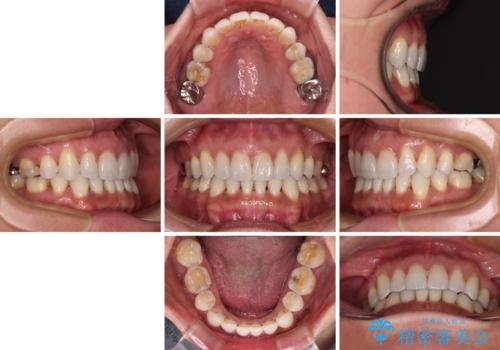

- 下顎前歯を中心に、以前行った矯正治療の後戻りが気になるとのことで来院された患者様です。

後戻りは軽度であったため、インビザライン・ライトにて治療を行うこととしました。

矯正治療後は、再度後戻りすることを極力回避するために、下顎前歯の舌側を細いワイヤーを用いて保定することとしました。